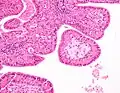

The appearance of this tumor under the microscope is unique. There are cystic spaces surrounded by two uniform rows of oncocytes, which are epithelial cells with abundant, granular, eosinophilic cytoplasm.[7] The cystic spaces have epithelium referred to as papillary infoldings that protrude into them. Additionally, the epithelium has lymphoid stroma with germinal center formation.

Histopathology of Warthin tumor in the parotid gland. Another view of a file "Warthin tumor (1).jpg". H&E stain.

Intermediate magnification micrograph of a Warthin tumor.